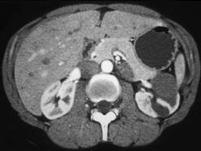

问题 女,35岁,请根据所示图像,选择最可能诊断 ( )

选项 A、左侧肾盂旁囊肿 B、左侧囊性肾癌 C、左侧高密度肾囊肿 D、左侧肾积水 E、左侧单纯性肾囊肿

答案 C